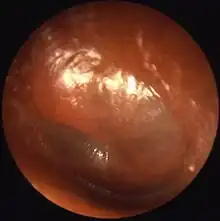

The ear drum may become perforated in the event of a large sound or explosion, when diving or flying (called barotrauma), or by objects inserted into the ear. Another common cause of injury is due to an infection such as otitis media.[35] These may cause a discharge from the ear called otorrhea,[36] and are often investigated by otoscopy and audiometry. Treatment may include watchful waiting, antibiotics and possibly surgery, if the injury is prolonged or the position of the ossicles is affected.[37] Skull fractures that go through the part of the skull containing the ear structures (the temporal bone) can also cause damage to the middle ear.[38] A cholesteatoma is a cyst of squamous skin cells that may develop from birth or secondary to other causes such as chronic ear infections. It may impair hearing or cause dizziness or vertigo, and is usually investigated by otoscopy and may require a CT scan. The treatment for cholesteatoma is surgery.[39]